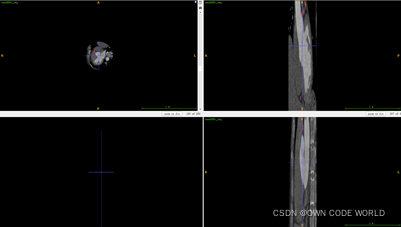

17.在这个模型中,测试出来的结果为下图.nii.gz格式的,因此我们可以使用ITK-SNAP软件来查看。

下面时使用ITK-SNAP软件来查看的结果图:

Img.nii.gz

pre.nii.gz

Img.nii.gz+ pre.nii.gz

Img.nii.gz+ gt.nii.gz

因为这组数据的dice有86%,所以效果还不错。